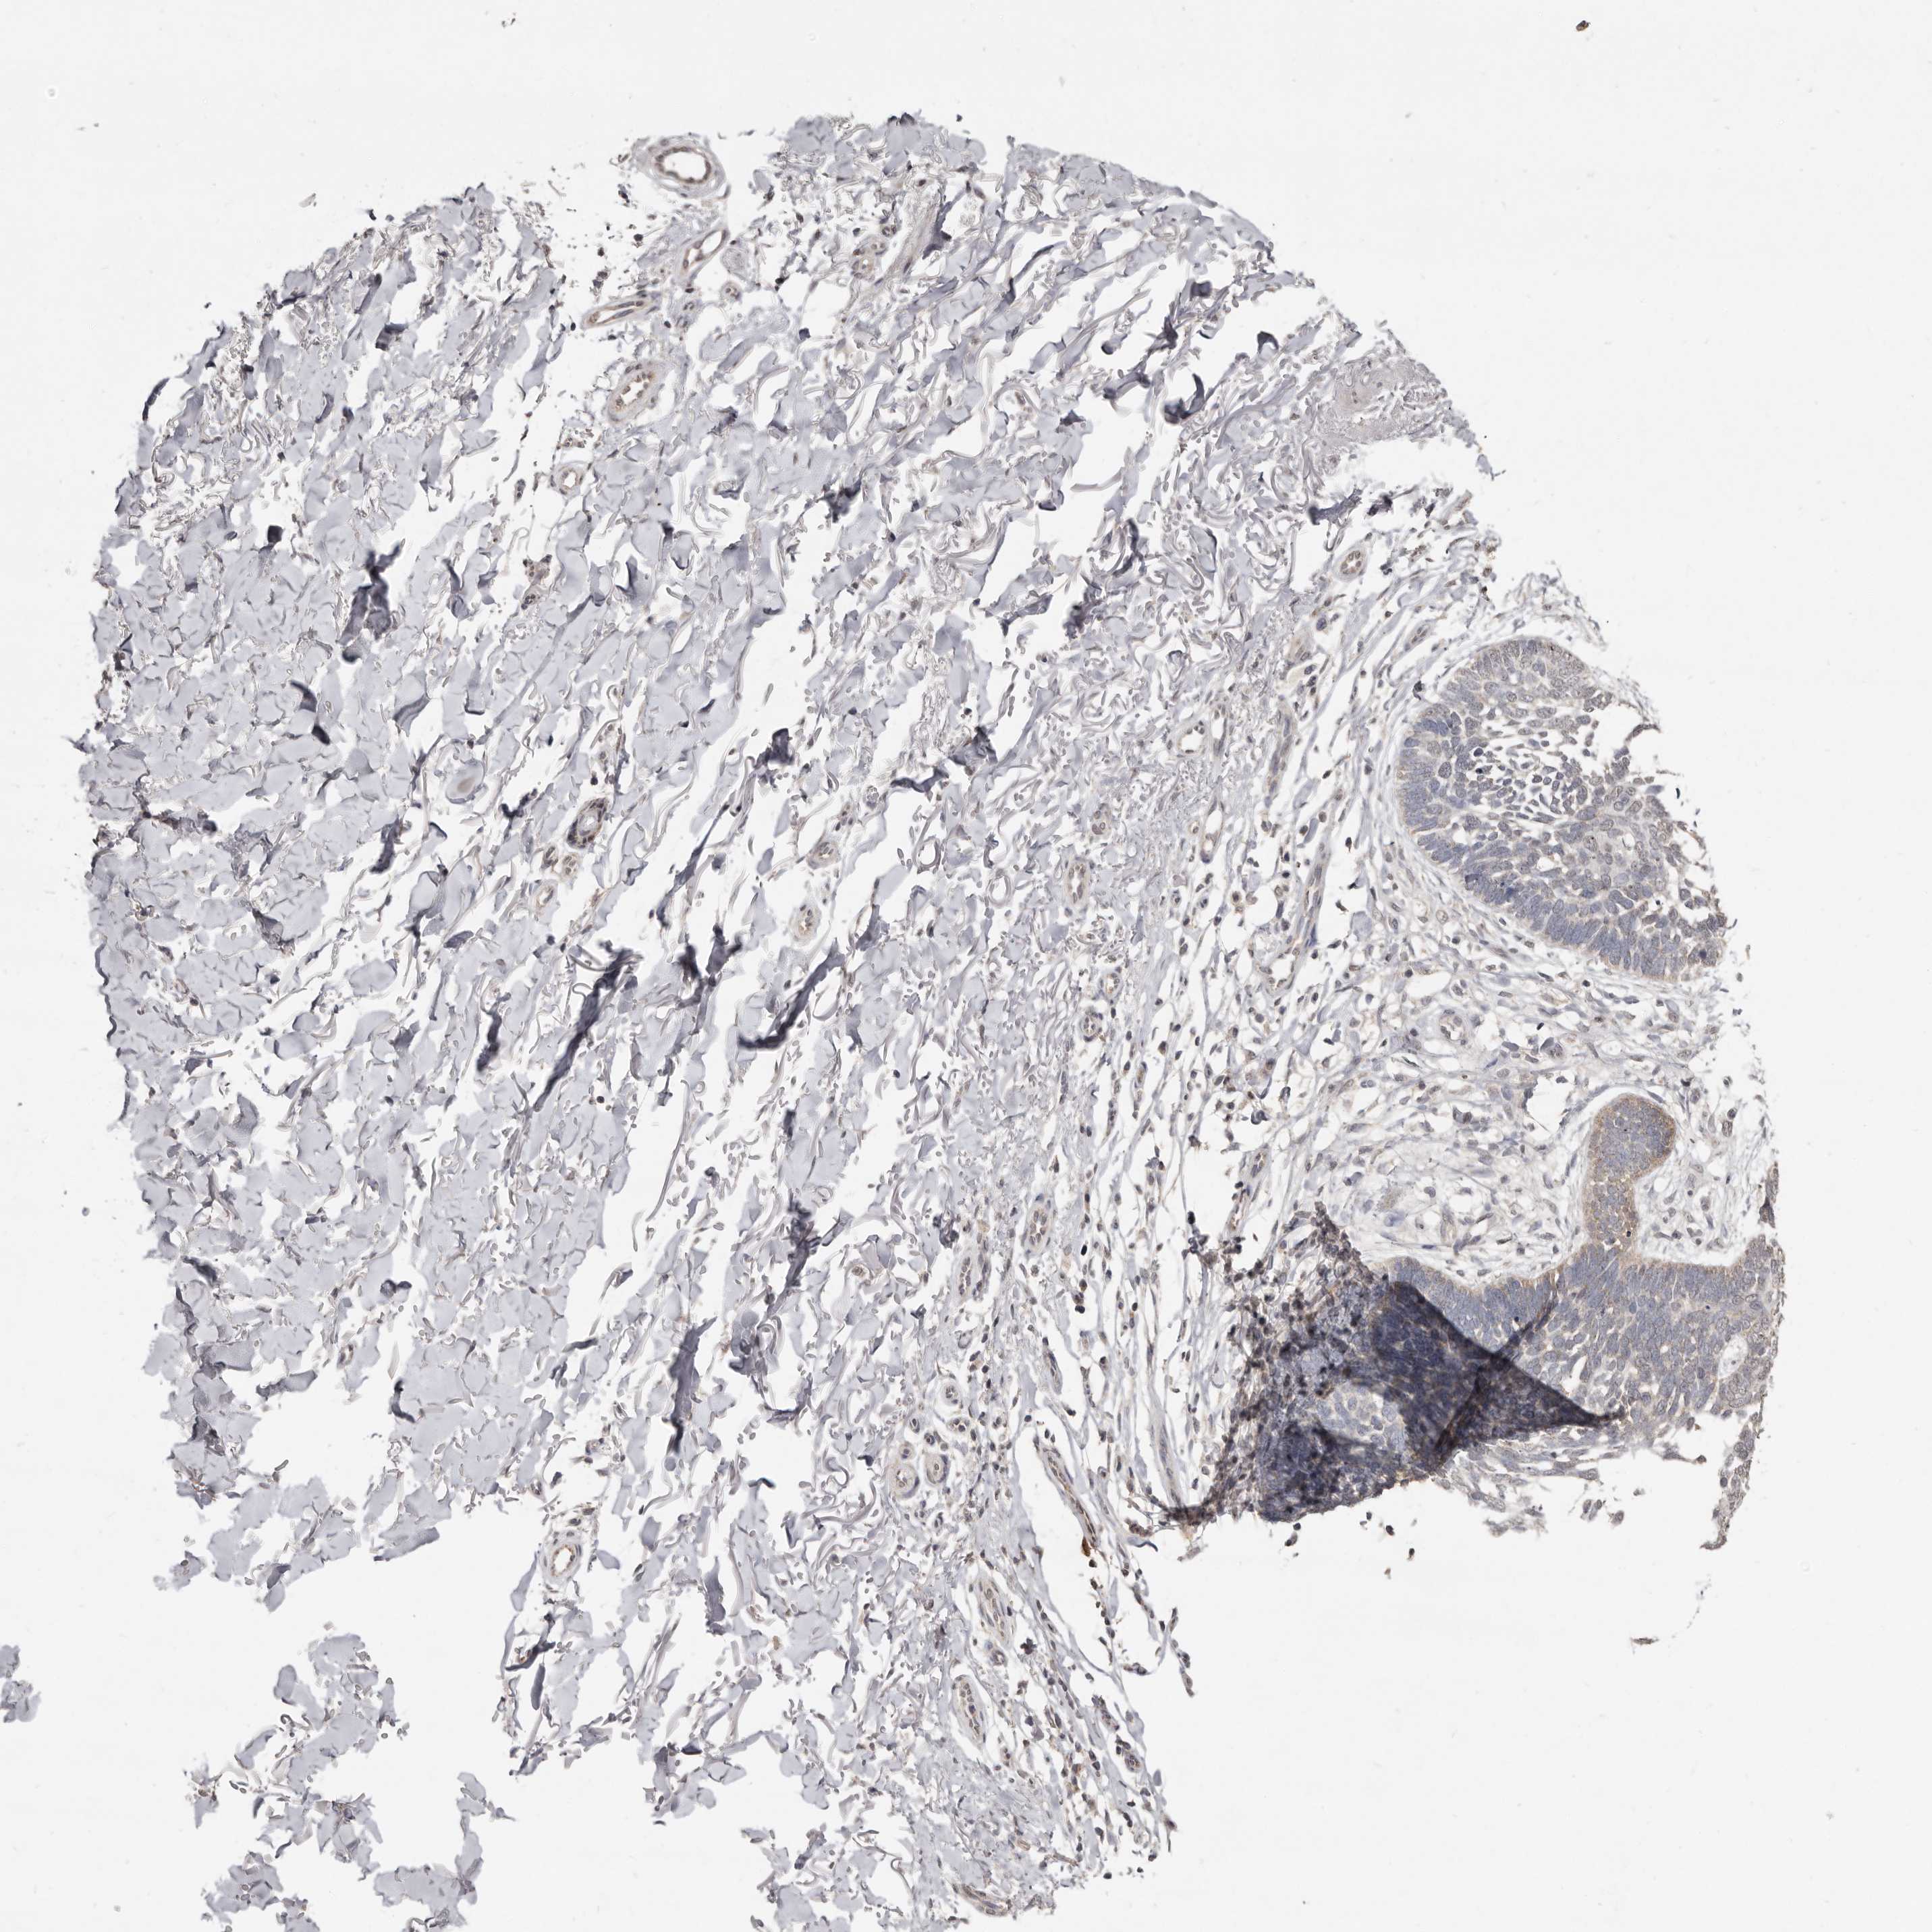

CANCER SKIN CANCER Show tissue menu

SKIN CANCER - Protein expressioni

A mouse-over function shows sample information and annotation data. Click on an image to view it in a full screen mode. Samples can be filtered based on level of antibody staining by selecting one or several of the following categories: high, medium, low and not detected. The assay and annotation is described here.

Each image is clickable and will lead to virtual microscopy that enables deeper exploration of all samples and also displays staining intensity scores, fraction scores and subcellular localization as well as patient and tissue information for each sample.

Antibody HPA016633

Squamous cell carcinoma in situ, NOS

Squamous cell carcinoma, NOS

Squamous cell carcinoma, metastatic, NOS

Basal cell carcinoma

Adnexal tumor, benign